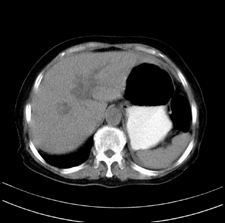

患者,女,75岁。腹痛,体黄5日,膝胸位时腹痛缓解。肝功能明日出来。彩超提示胆总管占位,未见血流信号。心电图提示s-t段改变。患者体质较弱,未能增强。

胆总管上段,腔内有软组织密度影 ,ct值36-44hu。大家看有没有胆管癌的可能。

典型胆总管多发结石;增强扫描前后ct值是否发生改变是鉴别结石与占位的依据。